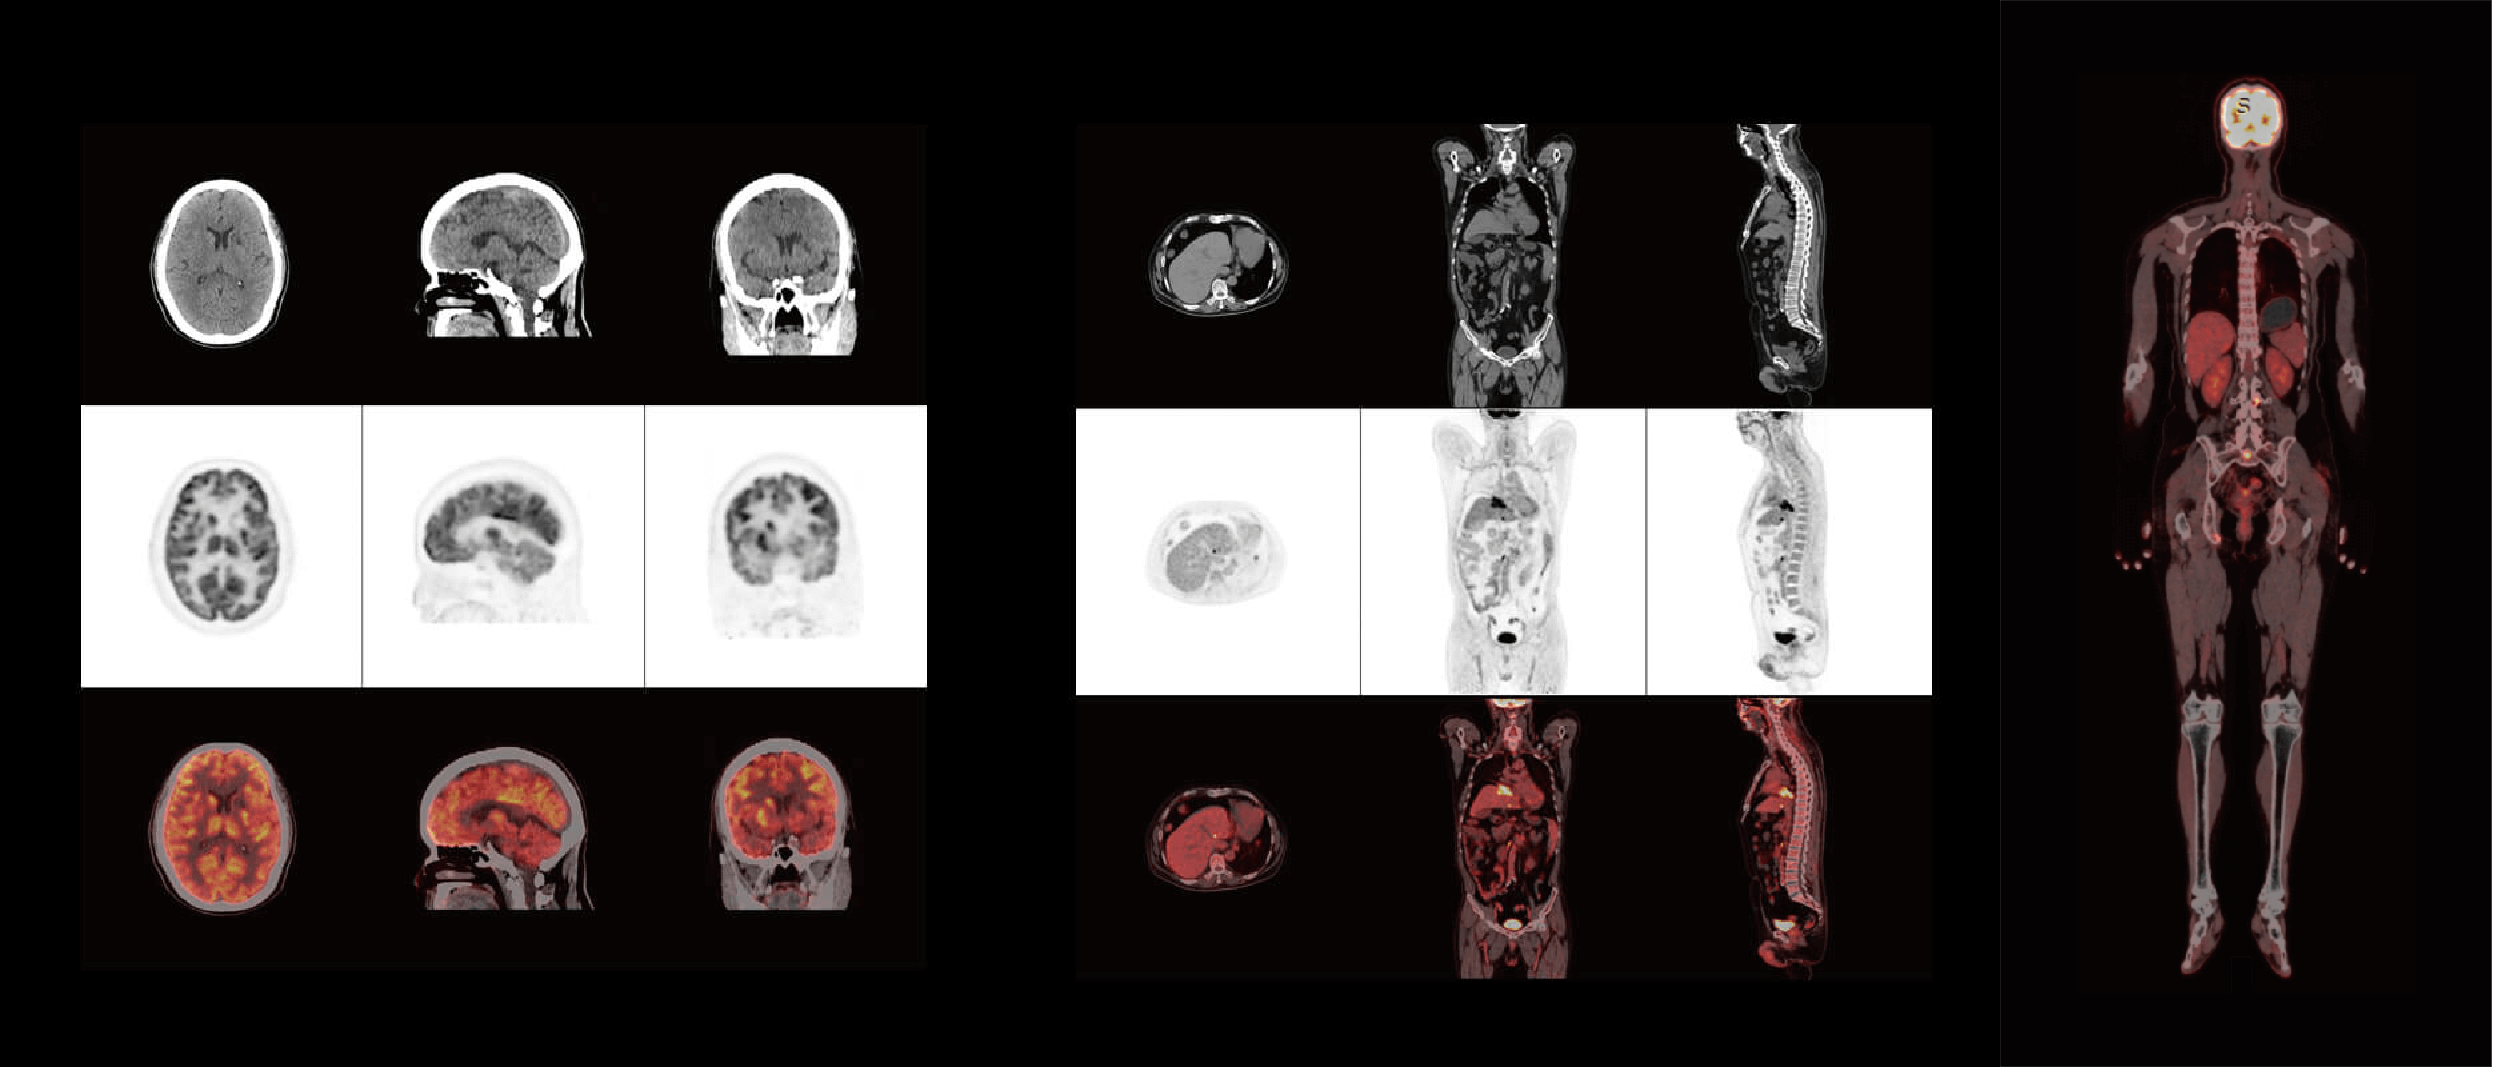

ScintCare PET/CT 720E

臨床畫廊